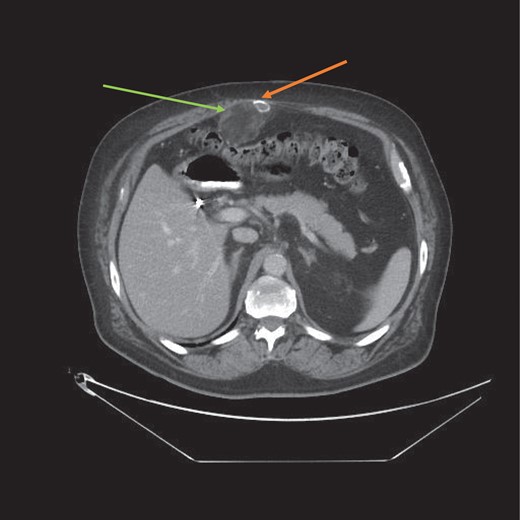

His medical history was significant for hypertension and alchoholism and both were well controlled. Radiological imaging included a computerized tomography (CT) scan which reported an internal hernia in the epigastrium (Figs 1 and 2). There were no radiological signs of bowel strangulation.

CT scan axial view of the myelolipoma (green arrow) with calcification (orange arrow). Abdominal wall musculature is intact thereby excluding an incisional hernia.

This was an incidental diagnosis based on a misinterpretation of the patient’s radiological imaging. Upon further discussion with our radiology colleagues, there was a consensus view that this was indeed a soft tissue tumour of the abdominal wall and not an internal hernia as originally reported. The author himself felt that this was an incisional hernia prior to surgery based on his clinical examination and original CT findings. Diastasis recti of the rectus abdominus musculature may also have contributed to the clinical confusion of an incisional hernia (Fig. 2). Given the rarity of this tumour, a soft tissue lesion was not entertained as an initial diagnosis.